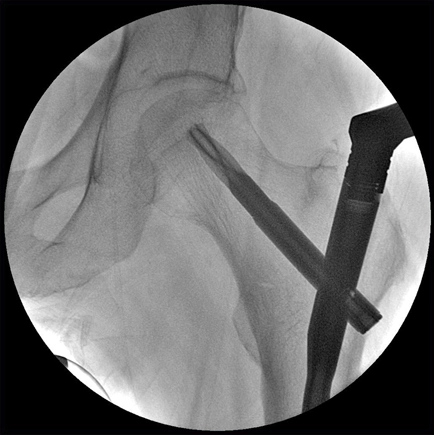

Полностью сбалансированная C-дуга для удобства маневрирования

Удобная в маневрировании C-дуга с большими диапазонами перемещения и поворота позволит получить доступ к пациентам любого телосложения. Система BV Vectra улучшает доступ при оперировании тучных пациентов даже в глубоких проекциях.